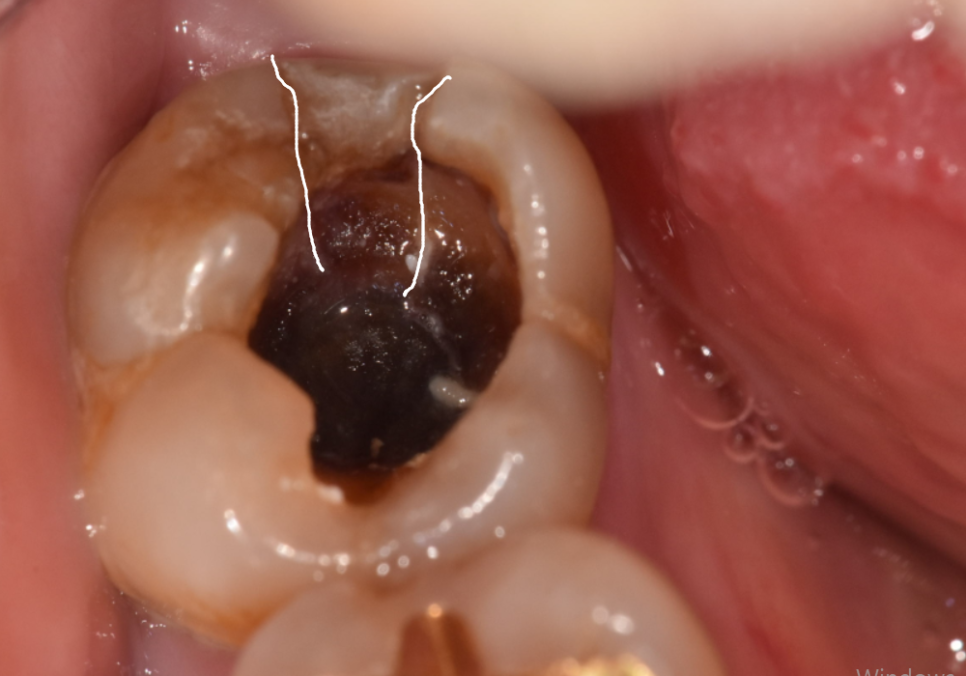

환자분은 오른쪽 아래

예전에 때웠던 보철물이 떨어졌는데,

통증을 참다가 오늘 치아에

금이 쫙 간 것 같다며

극심한 고통과 함께 내원하셨습니다.

오른쪽 아래는 수직 파절로 인해

치아 금이 쫙 가 있었는데요.

#47 치아: 수직 파절(완전히 쪼개짐)